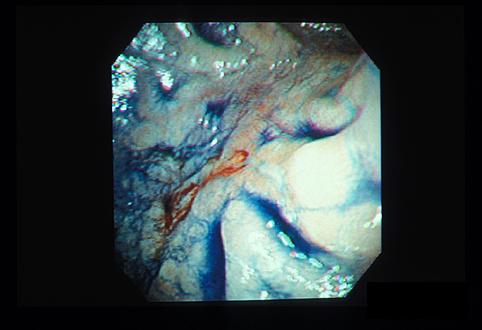

症例提示(所在地,施設名等): 東京都・ 国立がんセンター中央病院

疾患(病理主体)の分類悪性リンパ系腫瘍/悪性リンパ腫

部位(臓器別)十二指腸/球部

検査方法内視鏡

腫瘍の肉眼分類0型(表在型)/IIc型(IIc)

病変の最大径(ミリ)15〜19